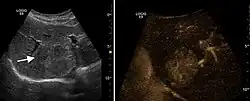

2D ultrasound, Doppler ultrasound and especially CEUS can play an important role in pretherapeutic staging, particularly when sectional imaging investigations (CT, MRI) provide uncertain results or are contraindicated. During the interventional procedure, ultrasound allows guidance of the needle into the tumor. CEUS allows guidance in areas of viable tissue and avoids intratumoral necrotic areas. CEUS also allows assessment of therapeutic effect immediately post-procedure (with the possibility of reintervention in case of partial response) . To accurately assess the effectiveness of treatment it is mandatory to compare the tumor diameter before therapy with the ablation area. The volume of damaged tissue must be higher than the initial tumor volume. CEUS appearance is that of central nonenhanced area showing a peripheral homogeneous hyperenhanced rim due to post-procedure inflammation. 24 hours after the procedure the inflammatory peripheral rim is thinning and the necrotic area appears larger than at the previous examination. Thus, a possible residual tumor may appear more evident. Residual tumor has poorly defined edges, irregular shape, and the tumor diameter is unchanged. Residual tumor tissue is evidenced at the periphery of the tumor as an eccentric area behaving as the original tumor at CEUS examination, with arterial hyperenhancement and portal and late wash-out. Ultrasound examination 24 hours after the procedure, including CEUS, can show apart from the character of the lesion any potential post-intervention complications (e.g. active bleeding).

In the first days after RFA both CEUS and spiral CT have low sensitivity in assessing therapeutic efficacy. CT sensitivity 24 hours post-therapy is reported to be even lower than CEUS. Difficulties in CEUS examination result from post-lesion hyperemia, presence of intratumoral air, ultrasound limitations (too deep lesion or the presence of fatty liver) or lack of patient's cooperation (immediately after therapy). For this reasons contrast imaging (CT or CEUS) control should be performed one month after ablation to confirm the result of the therapy.

Local recurrence is defined as recurrence of a hyperenhanced area at tumor periphery in the arterial phase, with portal and late wash-out. Sometimes, especially for HCC treated by alcoholization (PEI) hyperenhanced septa or vessels can be shown inside the lesion.